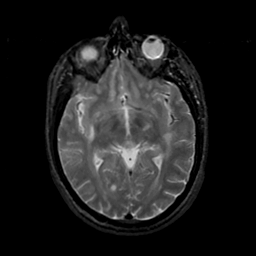

MR Study #18, July 21, 1991 -- Slice #23